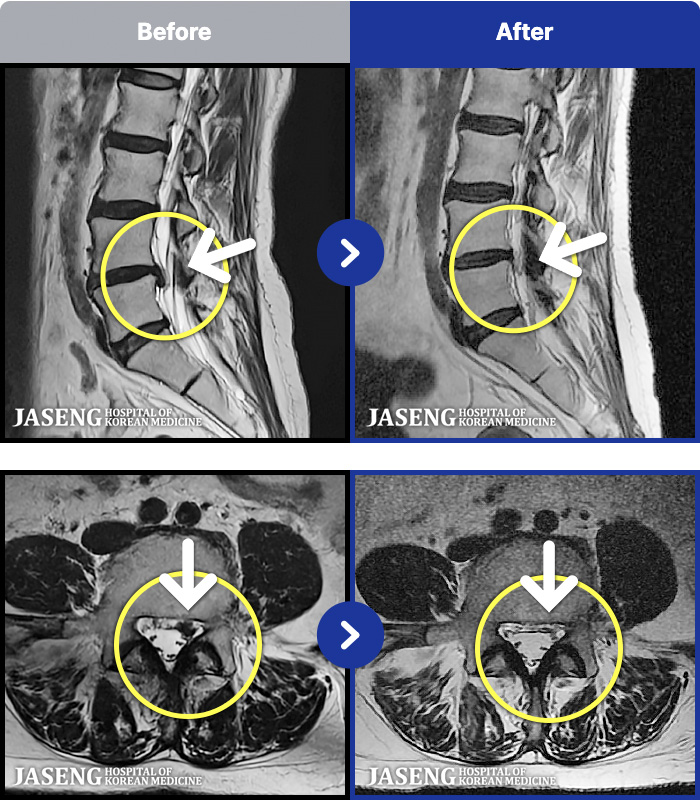

54 MRI ũ ʸ Ȯϼ.